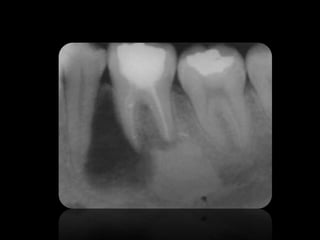

Interpretacion radiográfica

Clase de Interpretación Radiografica presentada por la Dra. Joyce Roca

3.

• Las imagenes

son llamadas radio opacas. • Las imagenes son llamadas radio lúcidas.

CARIES

ABSCESO PERIAPICAL